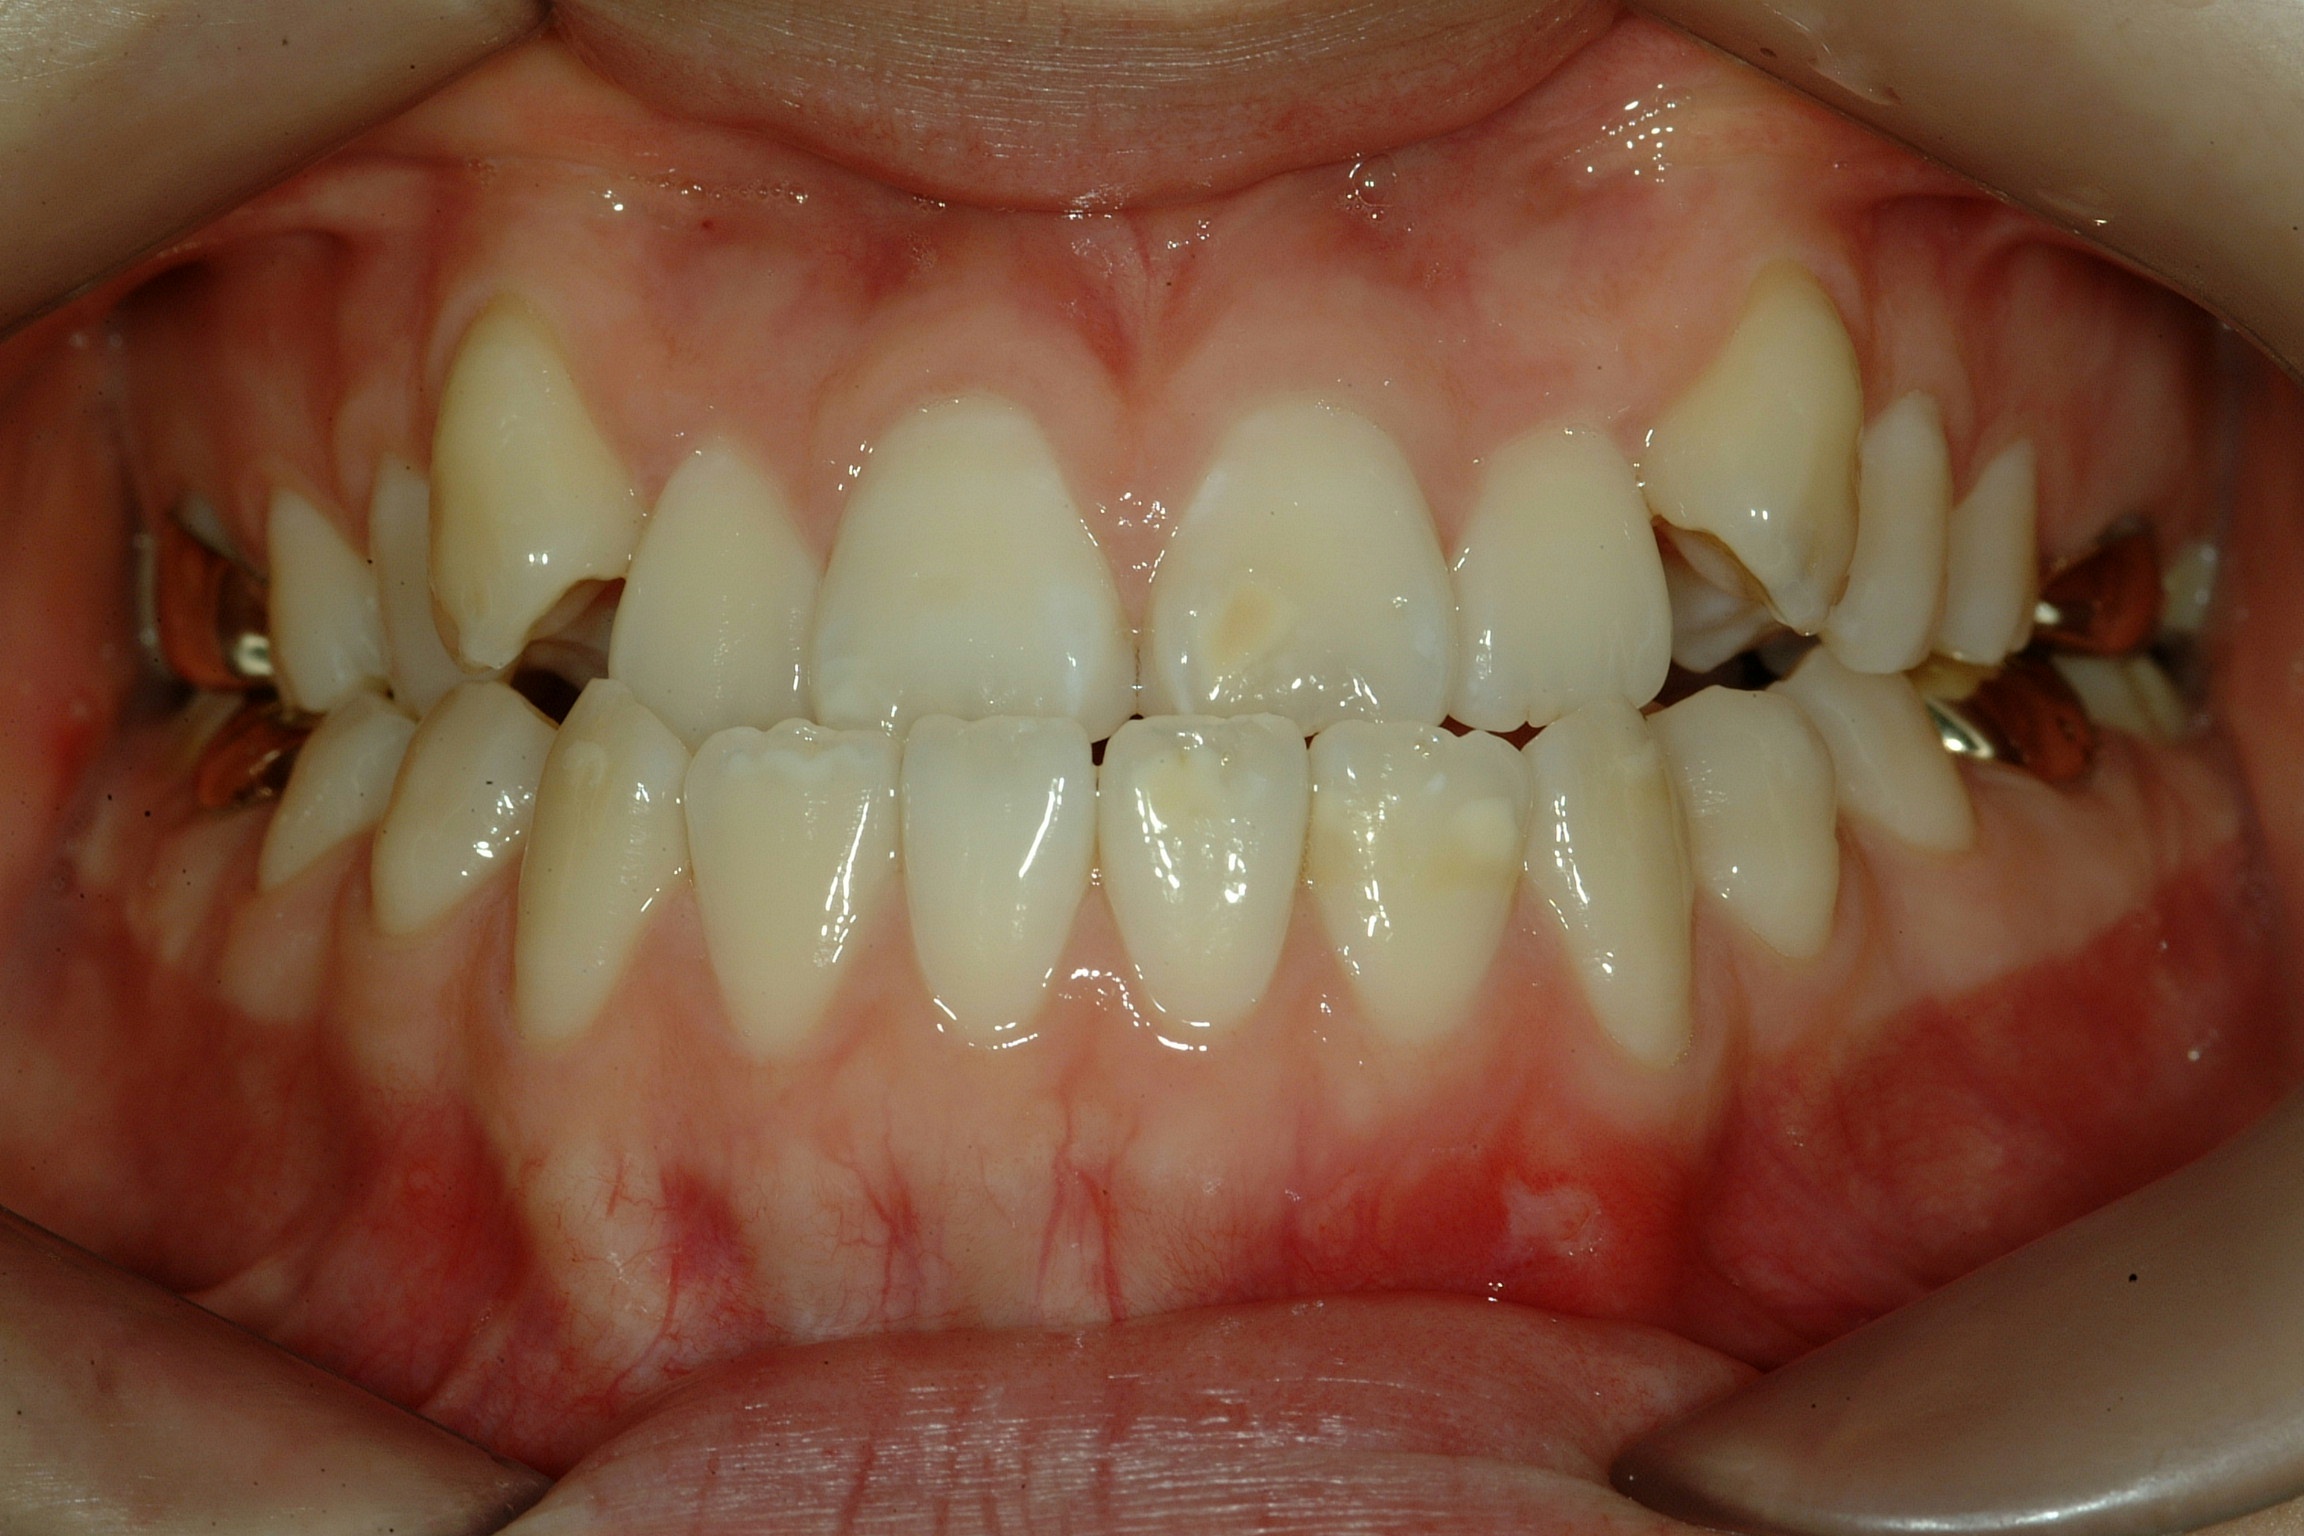

치료 전 사진입니다.